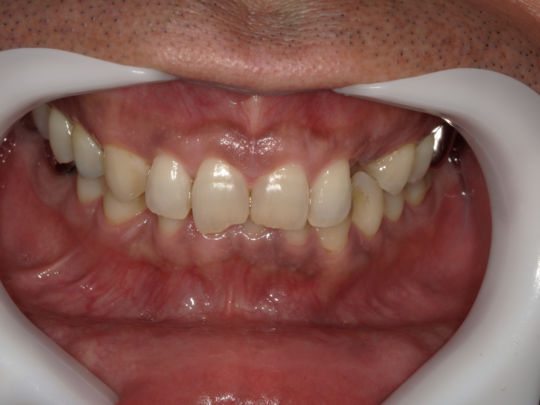

症例写真②

矯正前(正面)

矯正後(正面)

治療説明 歯科矯正でも目立ちにくい矯正方法です。透明に近いマウスピース型の矯正装置(アライナー)のため、歯に装着しても目立つことなく歯並びを矯正することが出来ます。また、一人ひとりの合わせて矯正装置を作製いたします。

治療期間 7か月

治療費用300,000 円

治療の副作用(リスク)歯の動き方には個人差があり、予想された治療期間が延長する可能性があります。。マウスピースの使用状況、矯正歯科治療には患者さんの協力が必要であり、それらが治療結果や治療期間に影響します。